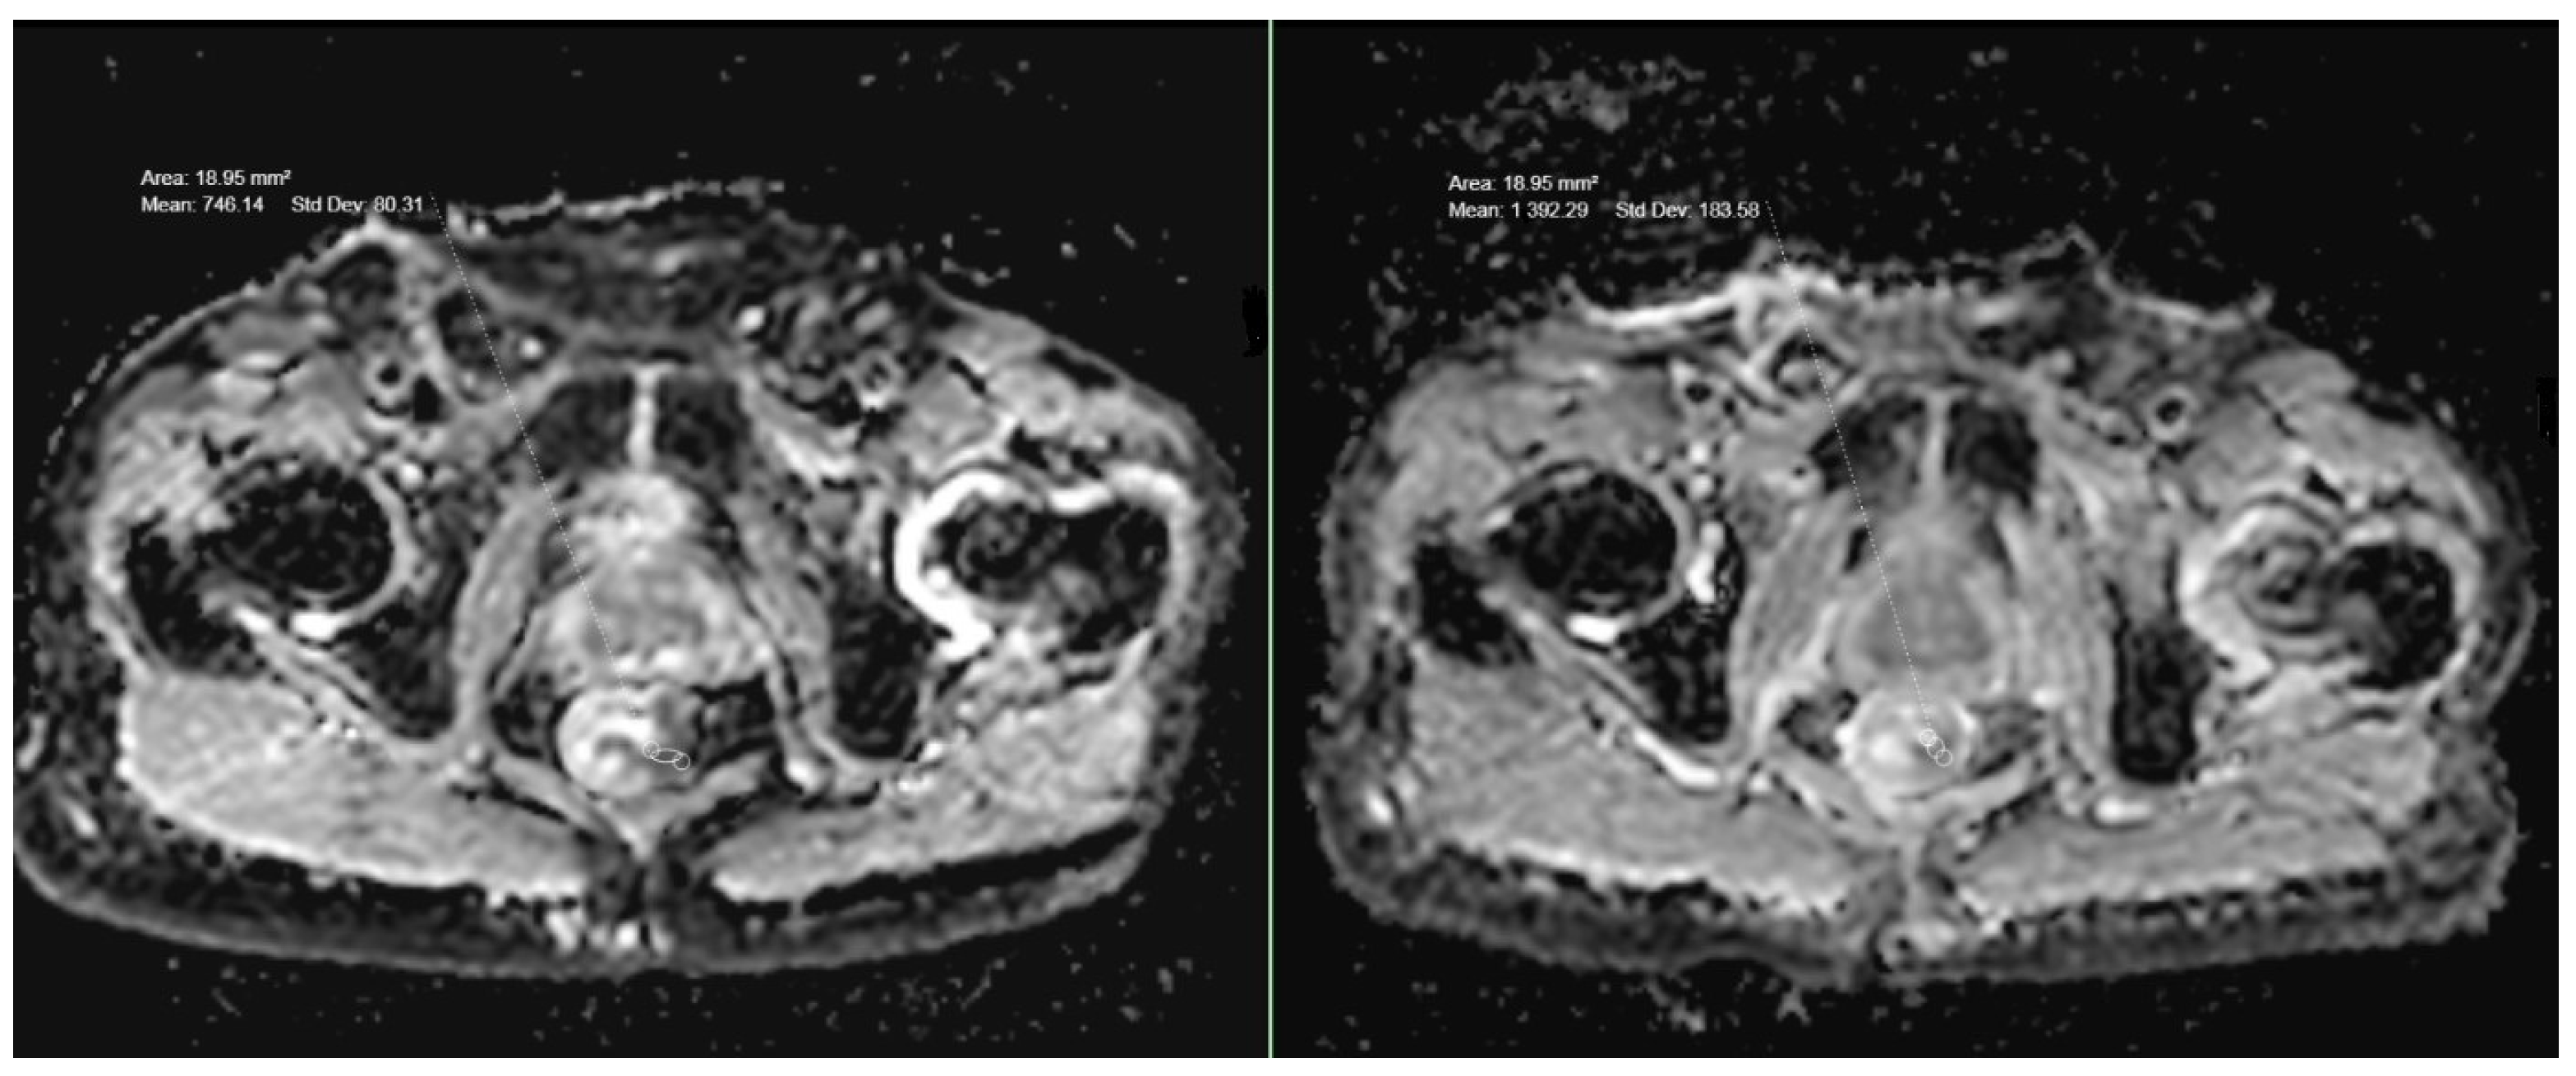

A statistically significant correlation was found when the ADC values in the rectal tumors of different T stages were compared (p = 0.039)—those with higher T stages showed lower ADC values (Figure 1b and Figure 2; Table 1). The mean ADC values in T1-stage tumors (5 patients) and T2-stage tumors (14 patients) were highest at 887 and 881, and the mean ADC value in T3 (38 patients) was 819 and in T4 (18 patients) was 776. No significant correlation was found between the ADC values of T3- and T4-stage tumors (p = 0.36) but T3- and T4-stage tumors showed significantly lower ADC values when compared to T1- and T2-stage (p < 0.05).

A statistically significant difference (p = 0.01) was found between the ADC values of 27 patients (36%) with extramural vascular invasion (EMVI) and patients without EMVI (Figure 1c; Table 1). The mean ADC value in patients with EMVI was overall lower (782) than the mean ADC of all 75 rectal cancer cases (841).

A total of 14 (78%) of all 18 patients who underwent neoadjuvant chemoradiotherapy (CRT) showed a partial response in the follow-up MRI with a >30% reduction in the size of the tumor. In three patients (16%), there was no significant difference in the size of the tumor, and in one patient (5%), there was a progression in the size. However, an increase in the ADC values was observed in all 18 cases (Figure 1d and Figure 3; Table 2). The mean ADC value after CRT was 1067. The mean increase in the ADC values after CRT compared to the initial ADC values was 241, which was shown to be highly significant (p < 0.001). The mean increase in ADC values in T2-stage tumors was higher (257; p < 0.05) than in T1- (202; p < 0.05) and T3-stage tumors (205; p < 0.05). Locally advanced T4-stage tumors showed the highest increase in ADC values (288; p < 0.05).

Figure 2. Pretreatment ADC value in a T3-stage rectal cancer.

Figure 3. ADC values in a case of T3-stage rectal cancer before and after treatment.